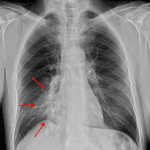

Age: 33

Sex: Female

Indication: Shortness of breath

Findings

- Blurring of the right heart border on the PA projection with a triangular opacity seen overlying the cardiac silhouette on the lateral projection

- Right IJ approach port catheter with tip projecting over the superior cavoatrial junction

- No pleural effusion or pneumothorax

- Normal size and configuration of the cardiopericardial silhouette

- Emphysema

Diagnosis

- Right middle lobe collapse

Right middle lobe collapse. Recommend followup imaging to ensure resolution. If there is persistent lobar collapse on followup imaging, chest CT should be obtained to assess for a fixed obstructive lesion.

- Right middle lobe collapse classically results in a triangular anterior opacity on the lateral view and hazy opacity with loss of the right heart border on frontal view

- Look for evidence of volume loss when trying to decide between atelectasis and consolidation. Signs of volume loss include hemidiaphragm elevation and hilar displacement toward the abnormality